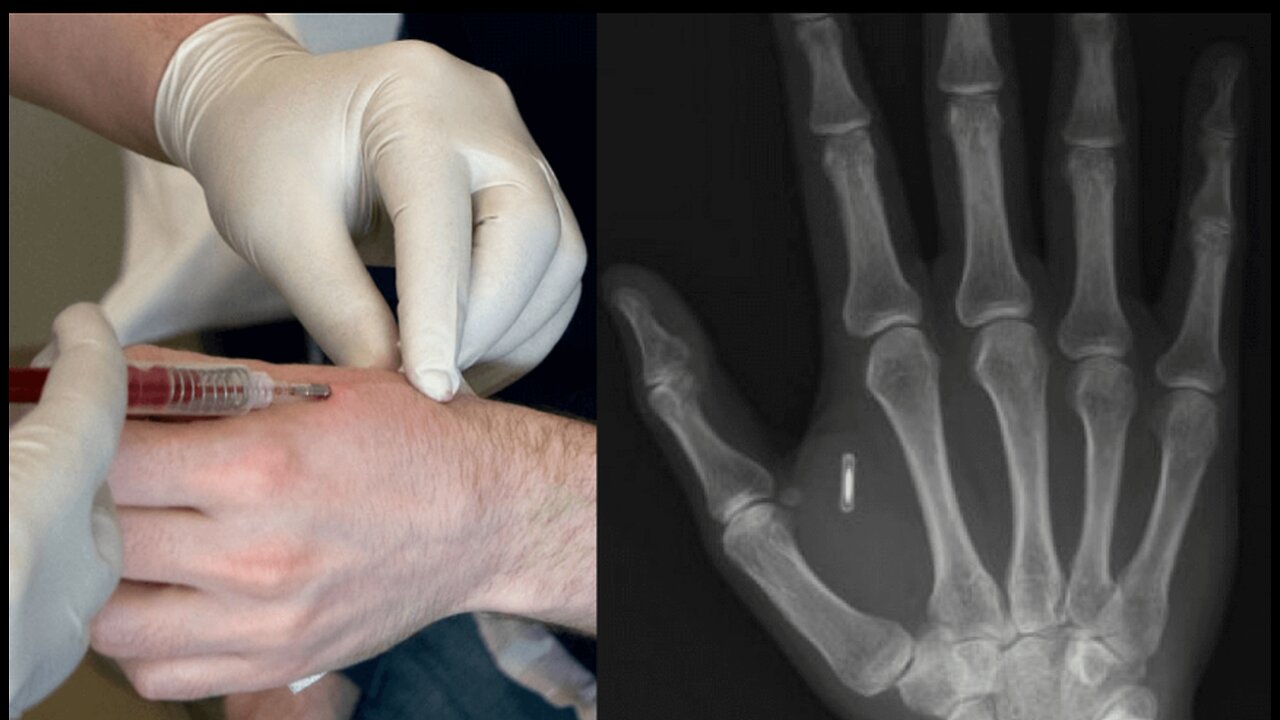

The RFID CHIP is THE MARK OF THE BEAST !!!!!!